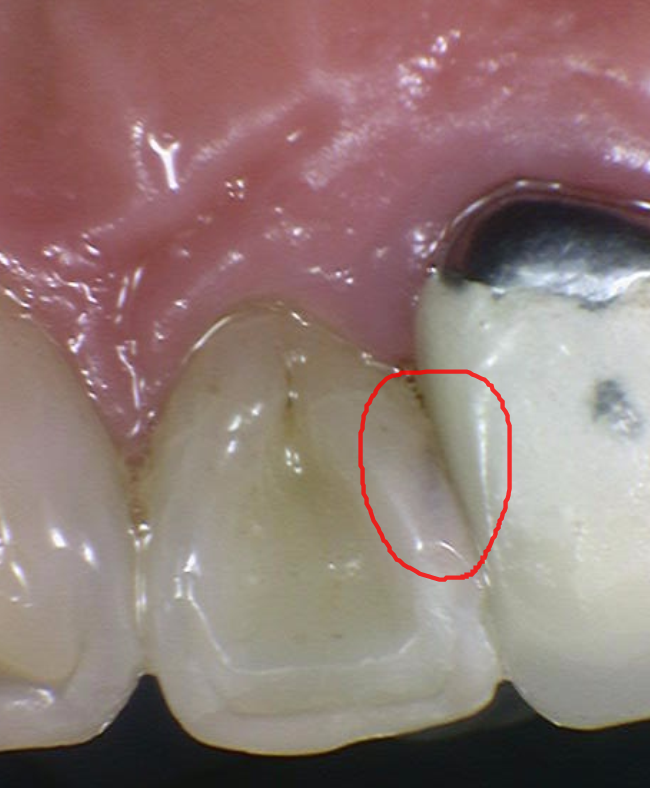

231127

조금만 손을 보았는데도 푹푹 들어가네요~~~

이것들을 깨끗하게 제거해주어야 재발도 없이

떼워줄 수 있습니다

충치 범위가 넓지는 않아

앞니 충치 레진으로 치료가 가능할 것으로 판단되었습니다.